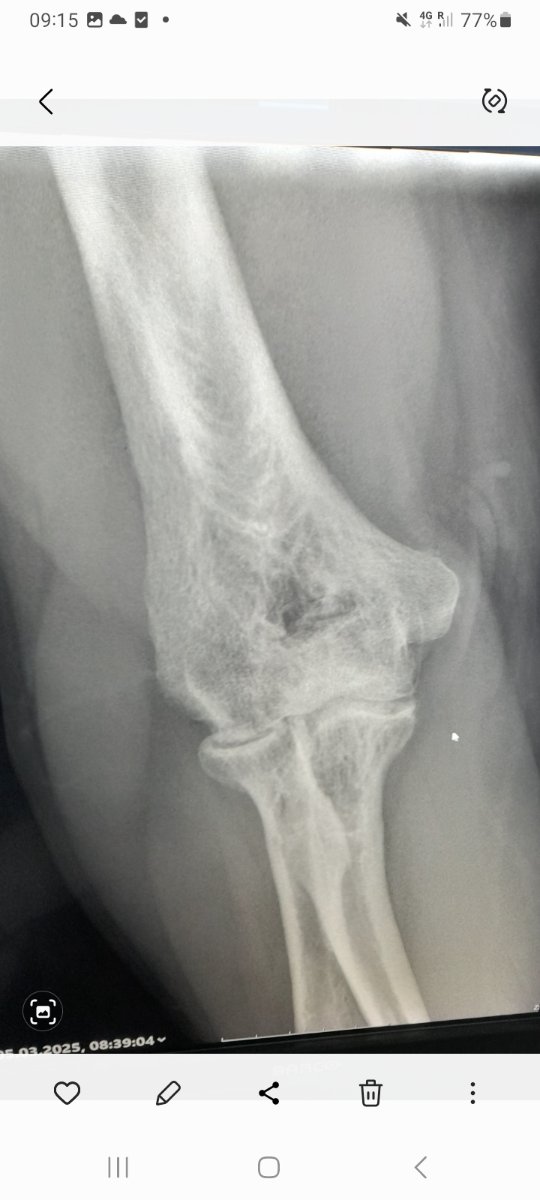

Inderdaad geen onverwacht nieuws...het is wat het is...ik wilde enkel een bevestiging hebben wat de oorzaak is waarom ik mijn rechterelleboog niet meer volledig kan strekken en die heb ik nu 🤭Klote allemaal René!, maar geheel onverwacht nieuws is het niet lijkt mij.....